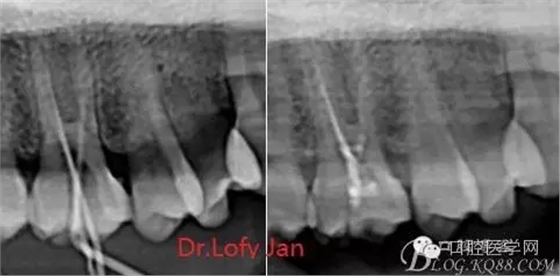

根管治療術(shù)是牙體牙髓疾病治療中最復雜和最關(guān)鍵的治療項目。根管充填材料抵達根尖、并能嚴密堵塞根尖孔,是確保根管治療效果的關(guān)鍵指標。為了保證根管充填到位,醫(yī)生需要在術(shù)前照牙片以了解牙根根管的數(shù)量、彎曲程度和長度,在術(shù)中有時需要插針照牙片來精確測量根管長度,術(shù)后必須照牙片以確定是否根管充填到位,如果欠填或超填,就需要重新充填、重新照牙片確認,直到根管充填到位。所以,在患者接受根管治療時有時會反復照牙片。

病例分析:曲面斷層片在x線輔助診斷與檢查中目前大多數(shù)文獻和著作都建議只能作為初診拍片檢查手段,不能作為終末疾病的確診與手術(shù)療效的評價指標,臨床大部分中小型門診都因為設備不齊全導致信息偏差很大。